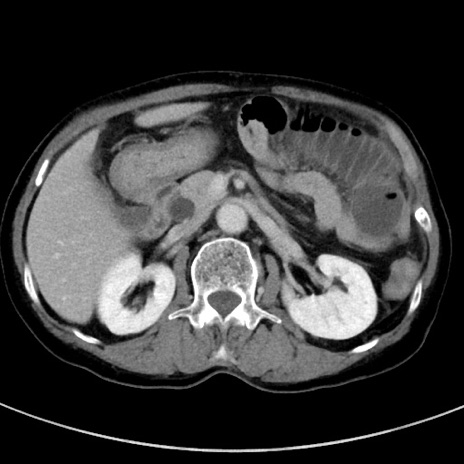

冠状断像

【症例】70歳代女性

【主訴】下腹部痛・嘔吐

【現病歴】2日前より腹痛あり。昨日嘔吐あり。症状改善しないため来院。

【既往歴】胃GISTに対して胃部分切除後。

【身体所見】BT 37.1℃、BP 128/77mmHg、腹部:平坦・軟、下腹部に圧痛あり。

【データ】WBC 10200、CRP 0.31